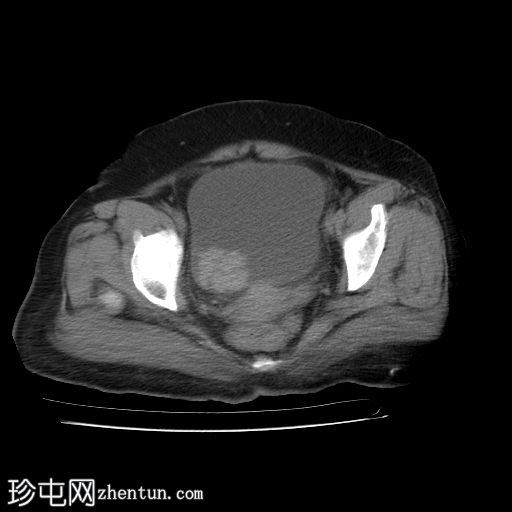

膀胱造影(静脉注射造影剂)

CT

轴位

平扫

膀胱内可见一边界清晰、不规则、可移动的软组织病变(CT值65 HU),直径约40 mm。病变无钙化,增强扫描后无强化。首要鉴别诊断为血肿。